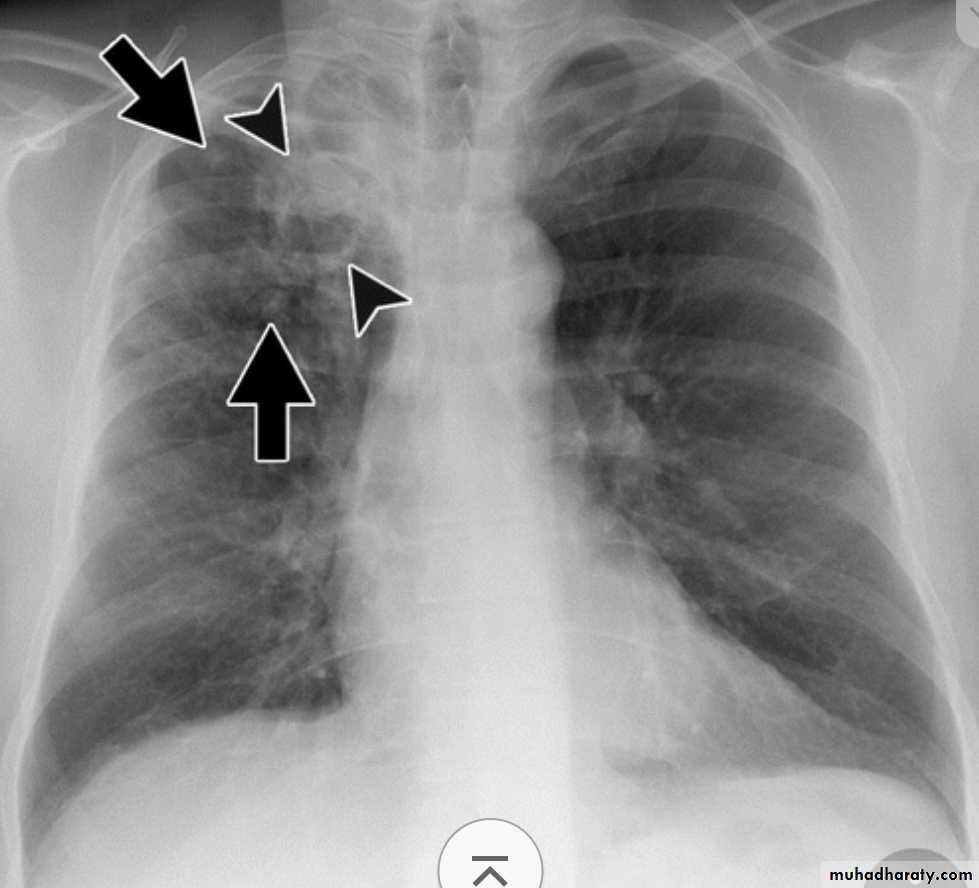

* Grossly: it forms a small sub pleural parenchymal lesion in the mid zone of the lung (Ghon focus) & spread to the hilar lymph nodes, both lesions are called Primary complex (Ghon complex).

Either occurs as a reinfection by mycobacterium TB or reactivation of primary infection when there is impairment in the immunity of the patient.Grossly: usually occurs at the apex of the lung with minimal lymph node involvement. There is marked damage in the lung parenchyma with cavity formation